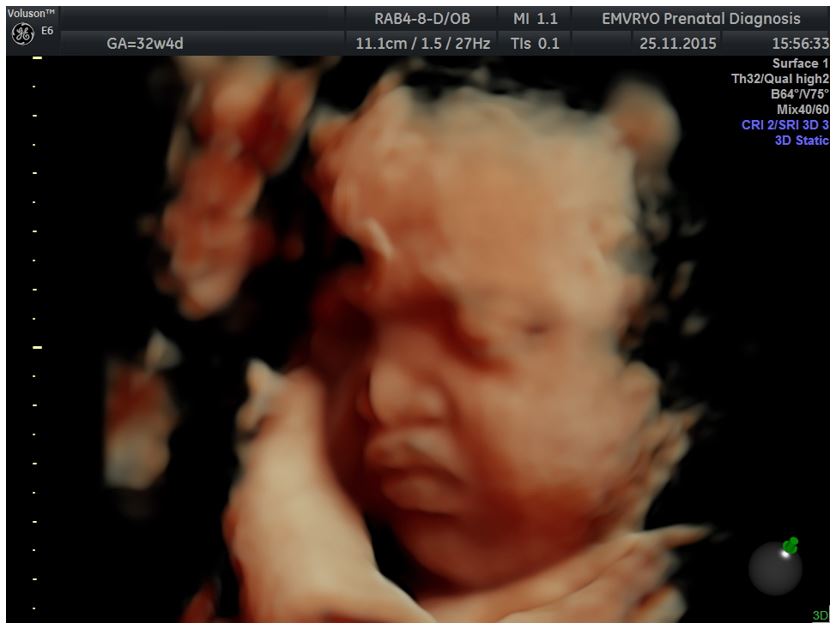

Figure 2: 3D reconstruction of the face in the same fetus at 32+4 gestational weeks

![A case of prenatally diagnosed Binder syndrome</br> [Apr 2017]](http://s834315022.websitehome.co.uk/wp-content/uploads/2020/11/cotm2017_april-fig02.jpg)